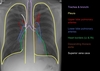

HF features on CXR?

* cardiomegaly * pleural effusions (due to fluid leak into the pleural space) * septal thickening - due to fluid leak into the intersitial space * consolidation due to fluid leak into the alveoli

HF signs are usually?

Summary of HF CXR?

* cardiomegaly, * small pleural effusions, * some septal thickening * and bilateral consolidation